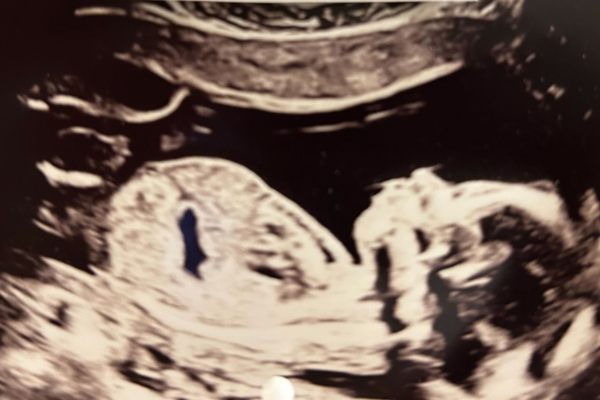

Gravid uge 17

Uge 17+0 – 17+6

Det går hurtigt nu, barnet er cirka 17 cm langt, og vægten ligger på omkring 190 gram. Fra nu begynder barnet at lagre fedt i kroppen. Det mangler nemlig næsten alt underhudsfedt. Fedtet fungerer lidt som en overlevelsesreserve for barnet og hjælper det med at holde varmen, når det er blevet født. Arme og ben er tynde – det meste af skelettet består stadig af blød og smidig brusk. I andet trimester er hjernens udvikling intensiv. Den beskyttes af sammensatte kranieknogler, der kan forskydes, således at pladsforholdene optimeres under fødslen, hvor barnet skal passere ned gennem fødselskanalen. De bløde områder på kraniet kaldes fontaneller og vokser først sammen i 2-3-års alderen. Øjenlågene dækker nu øjnene, og den lille kan mellem uge 24 og 27 åbne og lukke øjnene. Barnet opfatter sine omgivelser og kan reagere på høje lyde. Der er god plads og bevægelsesfrihed inde i livmoderen. Barnet vejer nu mere end moderkagen, og graviditeten kan med stor sandsynlighed ses.

En tidlig misdannelsesscanning kan laves nu. Har I sygdomme i familien, eller er du bekymret for dit barns udvikling, kan en tidlig misdannelsesscanning ofte skabe tryghed.